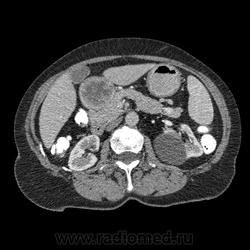

Впечатление, что дуля эта вне головки п.ж., интрамурально в луковице, что ли... тогда возможно GIST, но надо дайком. Утолщение подслизистой в антральном отделе желудка, не удается проследить переход от желудка к 12-перстной((. Внутрипросветно/внутристеночно - не разобрать. 1 фаза?

Клинику! Есть ли признаки высокой тонкокишечной непроходимости, что при ФЭГДС в 12-перстной - туда удалось пройти или нет? ААА! Одни вопросы))))

В-общем, варианты такие без дайкомов: пролапс слизистой в 12перстную, безоар, внутрипросветный дивертикул, гастроинтерстинальная опухоль. И большие сомнения, что это в головке п.ж. - оно отделено от неё тонким слоем жировой клетчатки

Фаз было 3. Видео не выставлял прошлый раз пришел ответ из сайта что видео не работает на сайте Идет накопление контраста в нативе в центре +2+4 по периферии +32+34 .в артериальную +20 и +65 +70 соответственно.

Что оно копит - бог с ним... если это пролапс слизистой, то суммация стенок. Безоар бы не копил. Напрягает отек слизистой в антрале... Это должно быть скорее внутри просвета кишки, т.к. оттесняет газ в 12-перстной на периферию. Без дайкомов больше ничем не могу, извините. Подождём мнения коллег.

Как мне видится - пролапс слизистой желудка в 12-перстную. А мнения коллег что-то нетути...

А что растет из левой почки? Может оно же и желудок сдавливает?

Это расширение всей 12- перстной кишки (стаз).